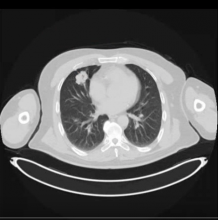

A 59-year-old asymptomatic man presented with a 3 cm NSCLC that was invading the upper and middle lobe fissure. PET and CT scans revealed no signs of extrathoracic disease or mediastinal lymph node metastasis.